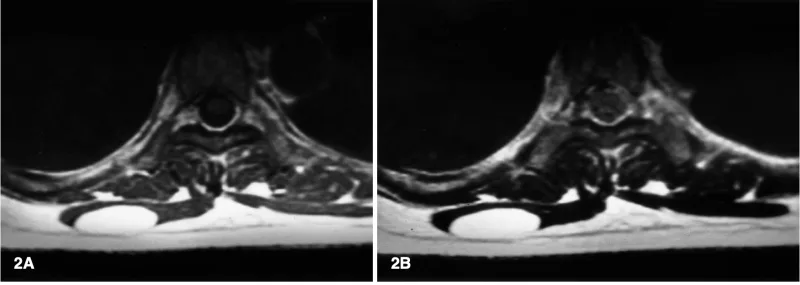

X線写真では, 腫瘍による骨破壊によって骨の中が透けるように黒っぽく写っていて, 内部に斑状の白い石灰化陰影を認めます.

MRI T2強調画像では, 水分含量の多い軟骨基質を反映して腫瘍部が白く描出されています.

1件目は, 第4足趾基節骨に生じた内軟骨腫.

軟骨性の良性骨腫瘍で, 骨の壁を切り取るように孔を開けて, そこから腫瘍を少しずつ削り取る手術(掻爬(そうは))を行いました.